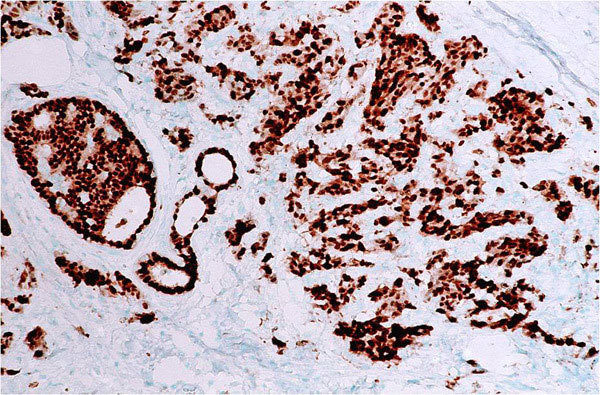

A measure of how rapidly a tumor is growing by assessing how many cells are dividing. The measure ranges from 0% (no cells dividing) to 100% (all cells dividing). (See also Ki67.)

An immunostain that marks a gene that is involved in cell proliferation or growth. The degree of Ki67 labeling in a cancer cell correlates to how quickly the tumor is growing and how aggressive it is. The measure ranges from 0% (no cells dividing) to 100% (all cells dividing). See also proliferation index.

A type of laboratory test that can detect the proteins expressed by a cell. The test uses special antibodies (“immunostains”) that each binds to a particular protein in question; the immunostain will change the color of the tissue to show whether a protein is present. Examples include immunohistochemistry to look for HER-2 overexpression, as well as the expression of the estrogen receptor (ER) and progesterone receptor (PR) in breast cancer cells.